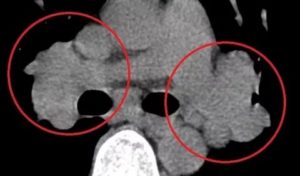

После комплексной диагностики врач определяет причины, которые повлекли увеличение узлов средостения. Лабораторные и инструментальные способы определят движущие силы нарушения. Данная патология исследуется способом компьютерной томографии (КТ), УЗИ (ультразвуковое исследование) грудной клетки, проведением МРТ (магнитно-резонансной томографии).

Больного с положительным результатом на иммунологический тест отправляют на КТ обязательно. Грудная клетка подвергается линейной томографии в исключительных случаях, когда нет альтернативы. Делают флюорографию, рентгеноскопию, выводят на табло прибора трёхмерный снимок.

Сегодня для диагностики средостенной лимфаденопатии применяют компьютерную визуализацию. При этой процедуре специалисты получают самую достоверную информацию. С помощью бронхоскопии медики получают материал для исследования трахеи, бронхов, туберкулёза. Радиография исследует кровообращение и вентиляцию лёгких.